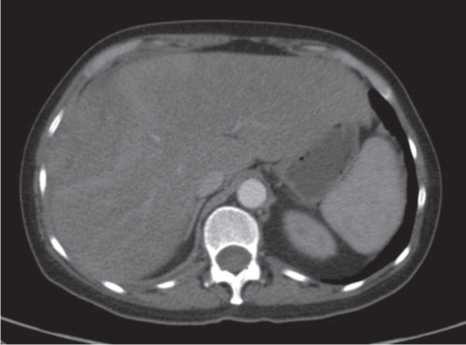

Рис. 3. КТ ОБП, начало контрастирования.

Fig. 3. Computed tomography (CT) scan of the abdomen, the beginning of contrast-injection.

Проведена компьютерная томография (КТ) органов грудной клетки, органов брюшной полости (ОБП), органов малого таза. По результатам обследования выявлено распространенное заболевание – многоузловая опухоль печени с множественными метастазами в легкие.

При первоначальной оценке функции печени пациент не имел признаков энцефалопатии, по данным КТ асцит незначительный, альбумин 32 г/л, международное нормализованное отношение 1,4, уровень общего билирубина 37,6 мкмоль / л.

Дигноз: ГЦР IV стадии T3BN0M1 гр. IV. Метастазы в легкие. BCLC С. Класс цирроза В по Чайлду–Пью.

На начало терапии имелся сливной таргетный очаг в печени с преимущественным поражением правой доли – 203 мм, нетаргетные очаги – метастазы в легкие до 5 мм, свободная жидкость в брюшной полости в незначительном количестве (рис. 3, 4).